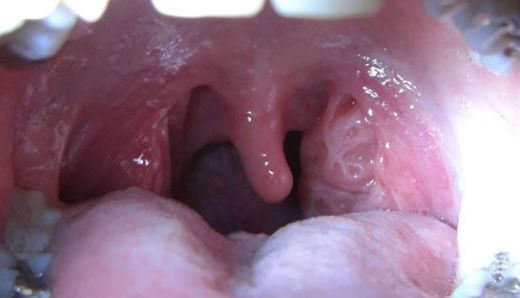

İltihaplı Bademcik Belirtileri ve Tedavisi

Bademcik Kızarıklığı Belirtileri ve Tedavisi

Bademcik Beyazlaması Nedenleri?